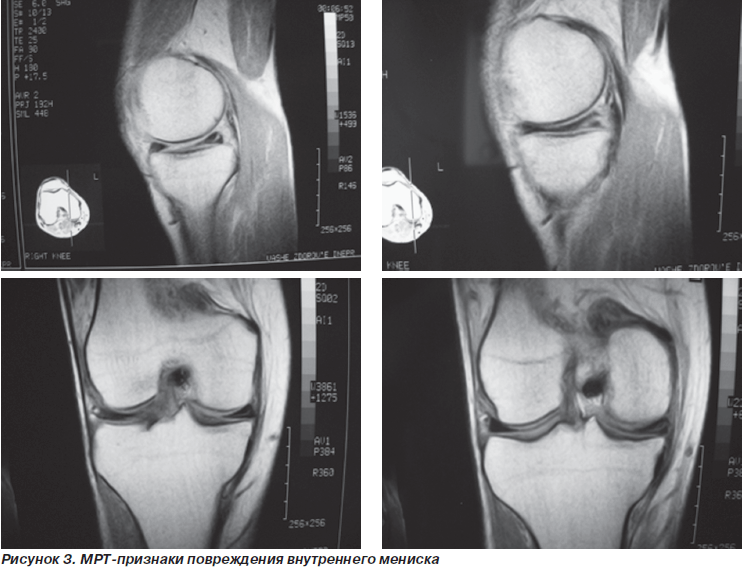

Разрывы внутреннего мениска по заключению МРТ были у 13 пациентов. При артроскопии у 12 из них разрыв был подтвержден. Всего при артроскопии выявлены 15 разрывов внутреннего мениска. То есть у трех больных повреждение внутреннего мениска на МРТ замечено не было. У данных пациентов имели место лоскутные разрывы внутреннего мениска.

МРТ-признаки повреждения наружного мениска наблюдались у 3 пациентов, что было подтверждено при артроскопии. Однако еще у 2 пациентов при артроскопии был обнаружен продольный разрыв в области заднего рога наружного мениска, что ранее при МРТ отмечено не было. По всей вероятности, данное повреждение на срезе МРТ сливалось с зоной, в которой наружный мениск в норме не имеет связи с капсулой сустава.

Неплохие результаты показала оценка данных МРТ при патологии менисков. Так, например, дегенеративные изменения менисков на начальных стадиях при артроскопии выявить, как правило, не удавалось, в то время как МРТ позволяла их определить.